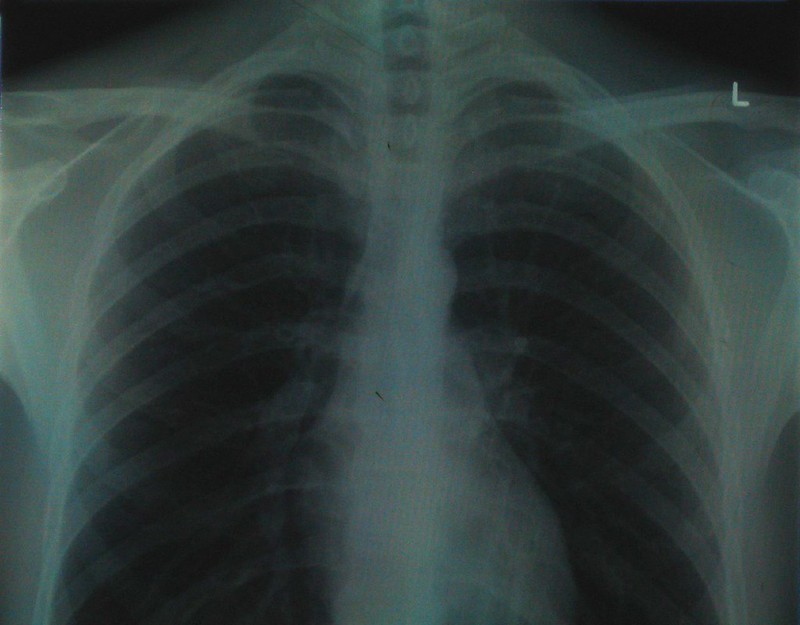

After I started having strange, sudden pains, I went to the ER and they took an x-ray. After demanding to know if I had ingested or ‘inserted’ anything, the doctor handed me the tablet.

A human hand was growing out of my torso, skeletal fingers distinct against my ribs.

“We’d like you to stay for observation,” he said. I agreed, silently fretting that this was too weird for insurance to cover.

Every day, the skeleton grew a little more, sprouting an arm, then a shoulder. Nothing the doctors tried worked, but eventually I left the hospital a whole new person.

chest x-ray half” by Aidan Jones is licensed under CC BY-SA 2.0.